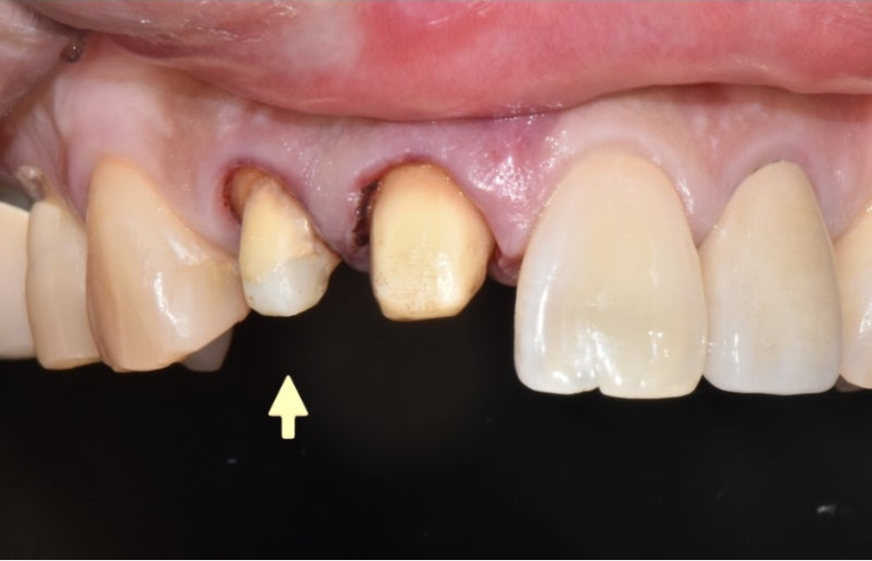

Hãy cùng xem trường hợp bệnh nhân dưới đây.

Bệnh nhân đến bệnh viện vì cắn đũa bằng răng cửa

khi đang ăn khiến mão răng cửa bị gãy.

▲ Thân răng bị gãy cùng với đầu răng

Do bên trong không có dấu hiệu sâu răng hay viêm nhiễm,

chân răng còn lại nằm sâu nên răng được cứu

bằng phẫu thuật kéo răng và

đặt lại mão răng.

▲Cứu chân răng bằng phẫu thuật kéo răng